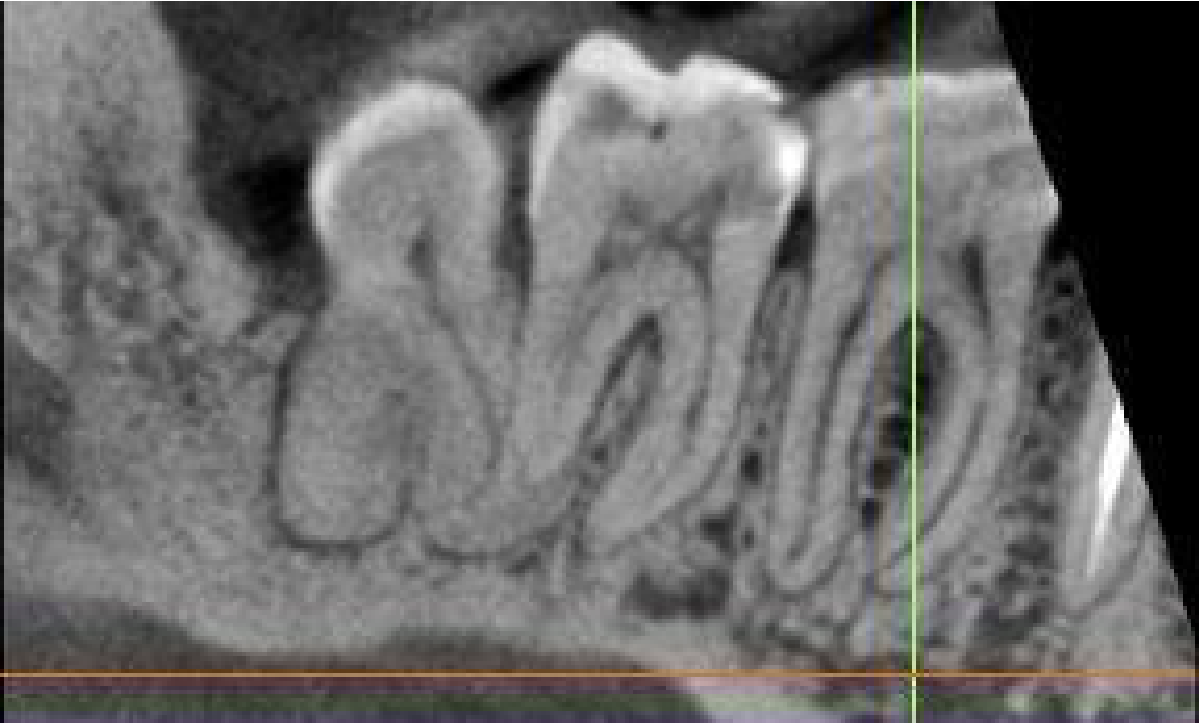

The LR6-8 have pulp stones.

Cropped panoramic of LR6-8 showing pulp stones in the LR6, LR7 and LR8.